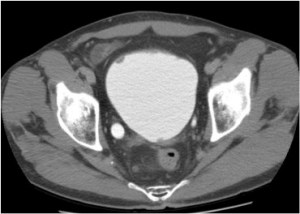

CASO CLÍNICO: Recopilatoción.

Paciente de 59 años con antecedentes personales de Cá de vejiga.

Se le realiza una Uro-Tc por seguimiento al año, aunque en esta ocasión el paciente refiere episodio de hematuria.

Tras el tratamiento de la recidiva y nefrostomía para la hidroureteronefrosis, vuelve acudir al hospital a los 9 meses por episodio de dolor en FD y malestar general. Se realiza una ecografía de urgencias.

Se realiza nueva TC bifásico abdominopélvio y Uro TC.